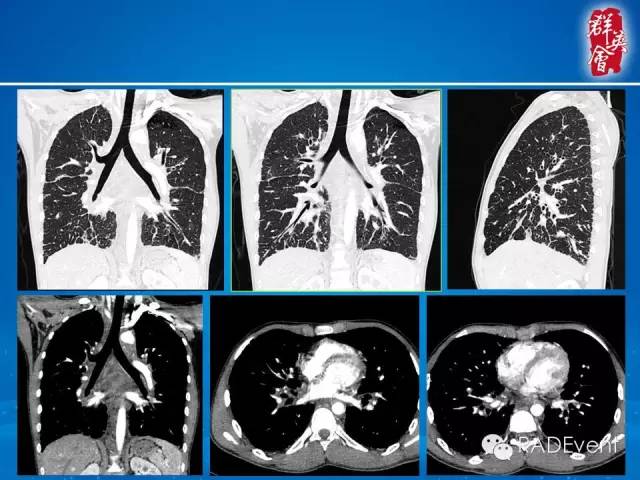

【病例】弥漫性肺淋巴管瘤病1例CT影像表现